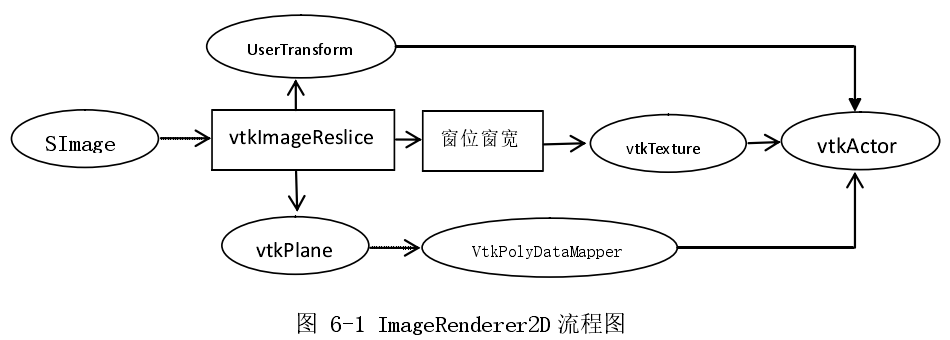

ImageRenderer2D 用来渲染二维图像格式,ImageRenderer3D 用来渲染三维图像格式,MeshRenderer2D 用来渲染二维多边形图像格式,Mesh Renderer3D 用来渲染三维多边形图像格式。以下是对以上 4 种渲染器的详细设计。

ImageRenderer2D 的主要功能是从三维图像数据中提取出对应的二维图像切片,并显示在二维视图上。其配置流程如下图(图 6-1)所示:

其中,vtkImageReslice 用于从三维体数据中提取出对应的二维切片,vtkTexture 用途是将 vtkImageData 图像转化为纹理数据,vtkPlane 是指 vtk 平面,VtkPolyDataMapper 用于渲染VtkPolyData 类型图像。